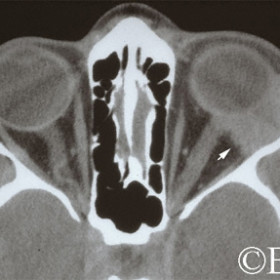

Adenoid cystic carcinoma of the lacrimal gland

Adenoid cystic carcinoma of the lacrimal gland (arrow).